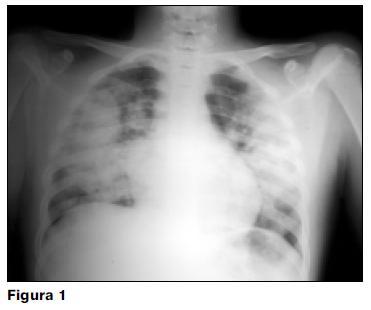

La hemorragia pulmonar, complicación rara (6%) y grave puede llevar rápidamente a la muerte (7). Ésta se observó en 1 caso de esta serie, falleciendo el paciente dentro de la primera semana del inicio de su enfermedad (radiografía de tórax: figura 1).

La hipertensión pulmonar es también una complicación grave y poco frecuente que puede llevar a la muerte por insuficiencia cardíaca descompensada (2,17). En esta casuística se presentó un caso de hipertensión pulmonar severa que revirtió en la evolución, sin complicaciones.